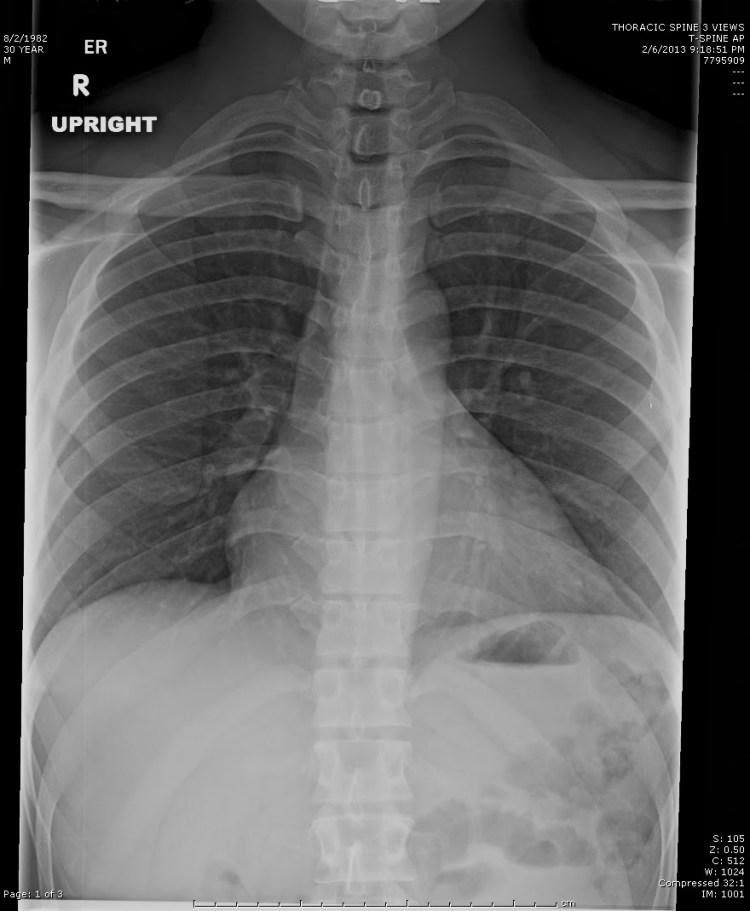

La tele de tórax es un estudio radiológico que se realiza con el paciente en posición erguida y a una distancia mayor del tubo de rayos X, lo que permite obtener una imagen más amplia del tórax. Esta técnica proporciona una mejor visualización de las estructuras anatómicas, reduciendo distorsiones y ofreciendo mayor detalle de los pulmones, el mediastino y el corazón.

- Mayor distancia foco-placa (generalmente de 1.8 a 2 metros), lo que minimiza el agrandamiento de las estructuras.

- Menor distorsión de la silueta cardíaca, permitiendo una evaluación más precisa del tamaño del corazón.

- Adecuada evaluación de la caja torácica, incluyendo costillas, diafragma y vértebras torácicas.

La radiografía de tórax es un estudio radiológico convencional utilizado en la evaluación inicial de diversas enfermedades del aparato respiratorio y cardiovascular. A diferencia de la tele de tórax, la radiografía de tórax suele realizarse con el paciente en diferentes posiciones (frontal, lateral o supina) dependiendo del estado clínico y la necesidad diagnóstica.

- Distancia foco-placa más corta, lo que puede generar una leve magnificación del corazón y otras estructuras torácicas.

- Alta sensibilidad para detectar anomalías agudas, como neumonía, derrame pleural, colapso pulmonar o fracturas costales.